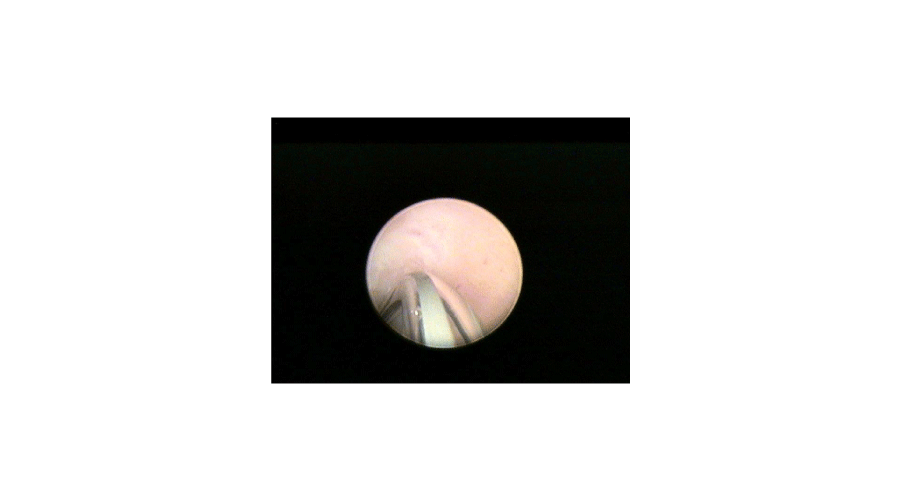

In the second step a 1.7 mm plastic catheter (Cavafix, B-Braun) is inserted through the working channel of the sheath and the tip is placed to the tubal ostium (Figures 1,2). During selective pertubation, each Fallopian tube is considered as a diagnostic unit. By rotating the hysteroscope, the direction of the catheter can be modified toward the ostium. The cone shape of the tubal ostium will help in leading the tip of the flexible catheter into the ostium. The catheter should not to be inserted into the tube, only the tip should be placed at the entry of it. Through the catheter 2-10 ml of methylene blue dye (Patente Blue, 2 ml in 1000 ml saline) is injected slowly. In case of a patent Fallopian tube no blue fluid will appear in the uterine cavity. Normal color of the endometrium can be seen, while the transparent catheter turns blue, due to the methylene blue flowing inside it (Figure 3). Occluded Fallopian tube changes the uterine cavity into blue, due to the back-flow of the methylene blue (Figure 4). In case of corneal occlusion, blue dye will flow back immediately. If the blockage is at the distal part of the tube, the first fraction of the blue dye will disappear and after some time of the injection will the back-flow be detectable. After the evaluation of tubal patency, blue dye clears up within 5-10 seconds and the whole procedure can be repeated on the other side. To be more exact and precise, transvaginal ultrasound examination should be performed before and after the hysteroscopy. This examination can exclude any pathology of the tubes that can cause false negative results, for example hydrosalpinx. By detecting free fluid around the ovaries and in the pouch of Doulas, the result of the perturbation can be verified. Total examination time is 4-8 minutes. As usual after office hysteroscopy, there is no need for post-operative observation, and the procedure can be performed with a high patient compliance [5].